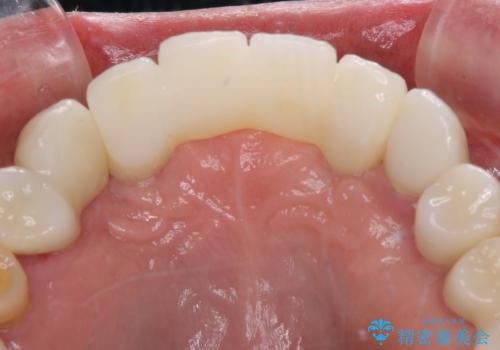

- 全顎的な歯肉からの出血と前歯の形態を気にして来院された患者様です。

診査の結果、上顎奥歯を中心に深い歯周ポケットが認められたため、歯周ポケット除去を目的とした歯周外科処置を行うこととしました。

歯周外科処置を行ったことで歯周ポケットはなくなり、毎回のブラッシングの度に嫌な思いをしていた出血は認められなくなりました。

上下前歯の見え方を気にされており、歯だけをみると大変長くなりましたが、笑ったときの口元は自然な外見となり、患者様には大変満足していただきました。